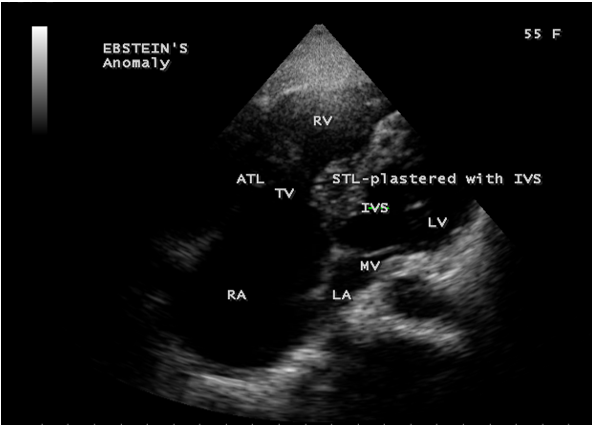

Case 3 (55-year old female with Ebstein’s anomaly)

A 55-year old asymptomatic, acyanotic female, given birth to three children, presented with grade 2/6 systolic murmur at the lower left sternal border. 2D echocardiography revealed a septal tricuspid leaflet tethering and a high moderate tricuspid regurgitation as shown in Figures 9 and 10 suggesting an Ebstein’s anomaly.

Echocardiographic features Echocardiography is the diagnostic test of choice for Ebstein’s anomaly and the first echocardiographic diagnosis was reported by Lundstrom in 1969. The first diagnostic criteria for Ebstein’s anomaly using a multi-crystal two-dimensional system was defined by Hagan in 1974 [33] and they were able to recognize the apical displacement of the septal tricuspid leaflet and an elongated anterior tricuspid leaflet with increased excursion. The septal leaflet of the tricuspid valve attaches chiefly to the ventricular septum , but part of its basal attachment is to the posterior wall of the right ventricle [34] and it normally exhibits a slight but distinct apical displacement of its basal attachment to the central fibrous body compared to the mitral valve. The distal displacement of septal origin of tricuspid valve seems to be the best echocardiographic criterion as the characteristic sign for Ebstein’s anomaly and the degree of maximal displacement in normal hearts varies considerably with a mean difference of approximately 6 mm with mitral valve. To define the anatomic severity of Ebstein’s anomaly, four-chamber view is the best to demonstrate the apical displacement of septal tricuspid leaflet [35]. The ratio between the mitral-to-apex distance and the tricuspid-to-apex distance varies from 1 to 1.2 in normal subjects and 1.8 to 3.2 in patients and it is 3.6 as in Figure 18 with Ebstein’s anomaly. The true distance in the level of insertion of atrioventricular valves is obtained by substracting the tricuspid-to-apex distance from the mitral-to-apex distance with a mean value of 27.25 ± 12 mm in patients with proven Ebstein’s anomaly and it is 60 mm as shown in Figure 18 compared to reference group (5.7 ± 2 mm). Kambe and coworkers calculated the distance between both atrioventricular valves directly as a mean value of 21 mm with a range of 14 to 32 mm [36]. A maximum difference in the level of valve insertion of >15 mm in children and >20 mm in adults is discriminated between normal and Ebstein’s anomaly [37],[38]. Despite this fact, a patient with an ‘unequivocal’ Ebstein’s malformation can be encountered in whom the diagnosis cannot be made with certainity solely on the basis of apical displacement of the septal tricuspid valve leaflet. Occasionally, the leaflet attaches to the trabecular part rather than the inlet part of the septum, the conventional four-chamber view will not reveal any septal insertion as shown in Figures 28 and 29.

The anterior tricuspid leaflet is not involved in the process of downward displacement, it may be abnormally inserted occasionally and Shiina, et al documented the apical displacement of anterior tricuspid leaflet in 14% of cases echocardiographically [39]. The anterior leaflet forms a large, sail-like intracavitary curtain as in Figures 14, 25 and contains muscular strands instead of consisting entirely of a fibrous membrane as in the normal tricuspid valve [40]. It is potentially mobile with a brisk sail-like movement as shown in Figure 21 to 24 [41], free bloating with a ‘whipping motion’ across the right ventricular outflow tract (RVOT) as shown in Figure 26 and in some cases, the movement is restricted due to its adherence to the ventricular wall as in Figure 1 and 2, 4 and 9. It is often fenestrated, may in part be musculaized , inserting into the trabeculations of the right ventricle (RV) as in Figure 28 and rarely, the anterior leaflet forms an ‘atretic’ membrane that spans the midportion of the right ventricular cavity as in Figure 16.

The tricuspid orifice is typically incompetent as in Figures 3, 5 and 10, occasionally stenotic, and rarely imperforate as in Figure 16 [44],[45]. The true anatomic tricuspid annulus occupies its normal position at the right atrioventricular junction and it is less well defined than in a normal heart. The annulus tends to be appreciably dilated and contribute to the development of valvular incompetence. In extreme downward displacement of posterior and septal leaflets, the closure of the tricuspid annulus depends on the size and potential excursion of anterior leaflet. When the chordal attachments are short and the leaflets contain multiple or large fenestrations, adequate valve closure is impossible to achieve and varying degrees of regurgitation results. Color flow imaging and Doppler interrogation can establish the relatively low velocity regurgitant flow as in Figure 6, which begins at the level of the displaced septal and posterior leaflets as in Figures 5 and 10 and courses through the atrialized right ventricle into the right atrium proper as shown in Figure 5. Tricuspid regurgitation increases by annular dilatation [46]. During contraction of the atrium, the atrialized portion of the right ventricle balloons out and acts as a passive reservoir. Functional improvement of right ventricle depends on the severity of tricuspid regurgitation and on the ratio of the combined areas of right atrium and atrialized right ventricle relative to the areas of functional right ventricle and left ventricle [47]. Celermajer, et al described an echocardiographic grading score for neonates with Ebstein’s anomaly as shown in the Table 5 [48].